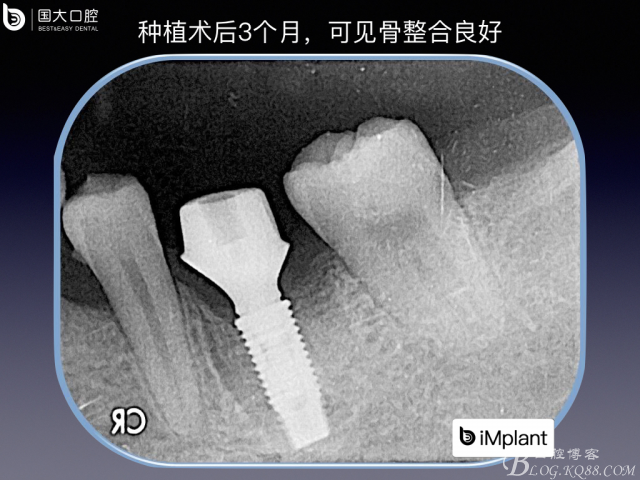

下頜磨牙的即刻種植位點(diǎn)設(shè)計(jì)

來(lái)源于國(guó)大口腔 邵現(xiàn)紅醫(yī)生發(fā)表的博文